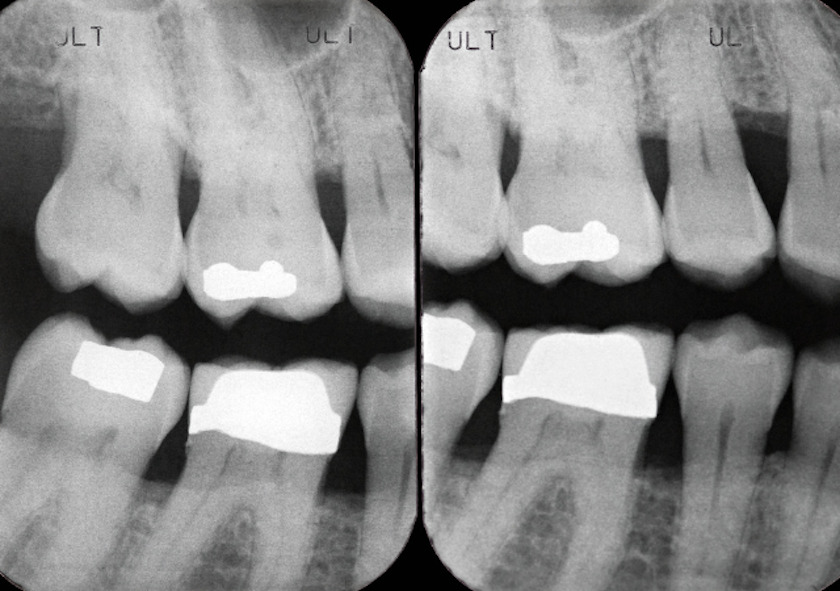

歯槽膿漏の治療前にはポケット測定やレントゲン撮影などで検査し、歯周病の進行度合いに応じて以下の治療を行います。

- スケーリング

- SRP(スケーリング・ルートプレーニング)

- 歯周外科処置

- 歯周組織再生療法

- 抜歯